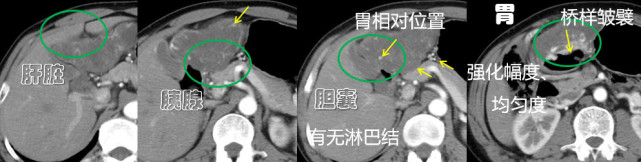

老杨的这个病例,因为他的肿瘤较大,又处在上腹部这个脏器众多的区域,导致和肝胆胰胃都分界不清,那么肿瘤到底是哪起源的?不同脏器来的肿瘤治疗可能是差别很大的,所以确认起源脏器进而做出准确诊断,对临床治疗是非常重要的。

在这个病例中我们用的一个手段就叫“本源血供征”。找不到是哪个脏器来的,就找它的血供,看看谁给它供血,那么谁就是孕育这个肿瘤的母体,跟胎儿和脐带的关系类似。后来追到血管是从胃发出来的,我就认为这个肿瘤是胃上长出来的。

确定了脏器,这还只是第一步。

图片(老杨腹部CT片分析)

第二步就要判断肿瘤是从胃哪层起源的,胃有黏膜(分泌胃酸)和肌层(研磨食物)两个功能层,不同层次起源的肿瘤类型也是不一样的。我们再根据“桥样皱襞”这个征象来判断,肿瘤是从黏膜下来的,从而除外了胃癌的可能性。

第三步再根据它的强化、均匀度、相对位置、有无肿大淋巴结等一系列的征象,最后诊断为胃肠间质瘤(GIST)。